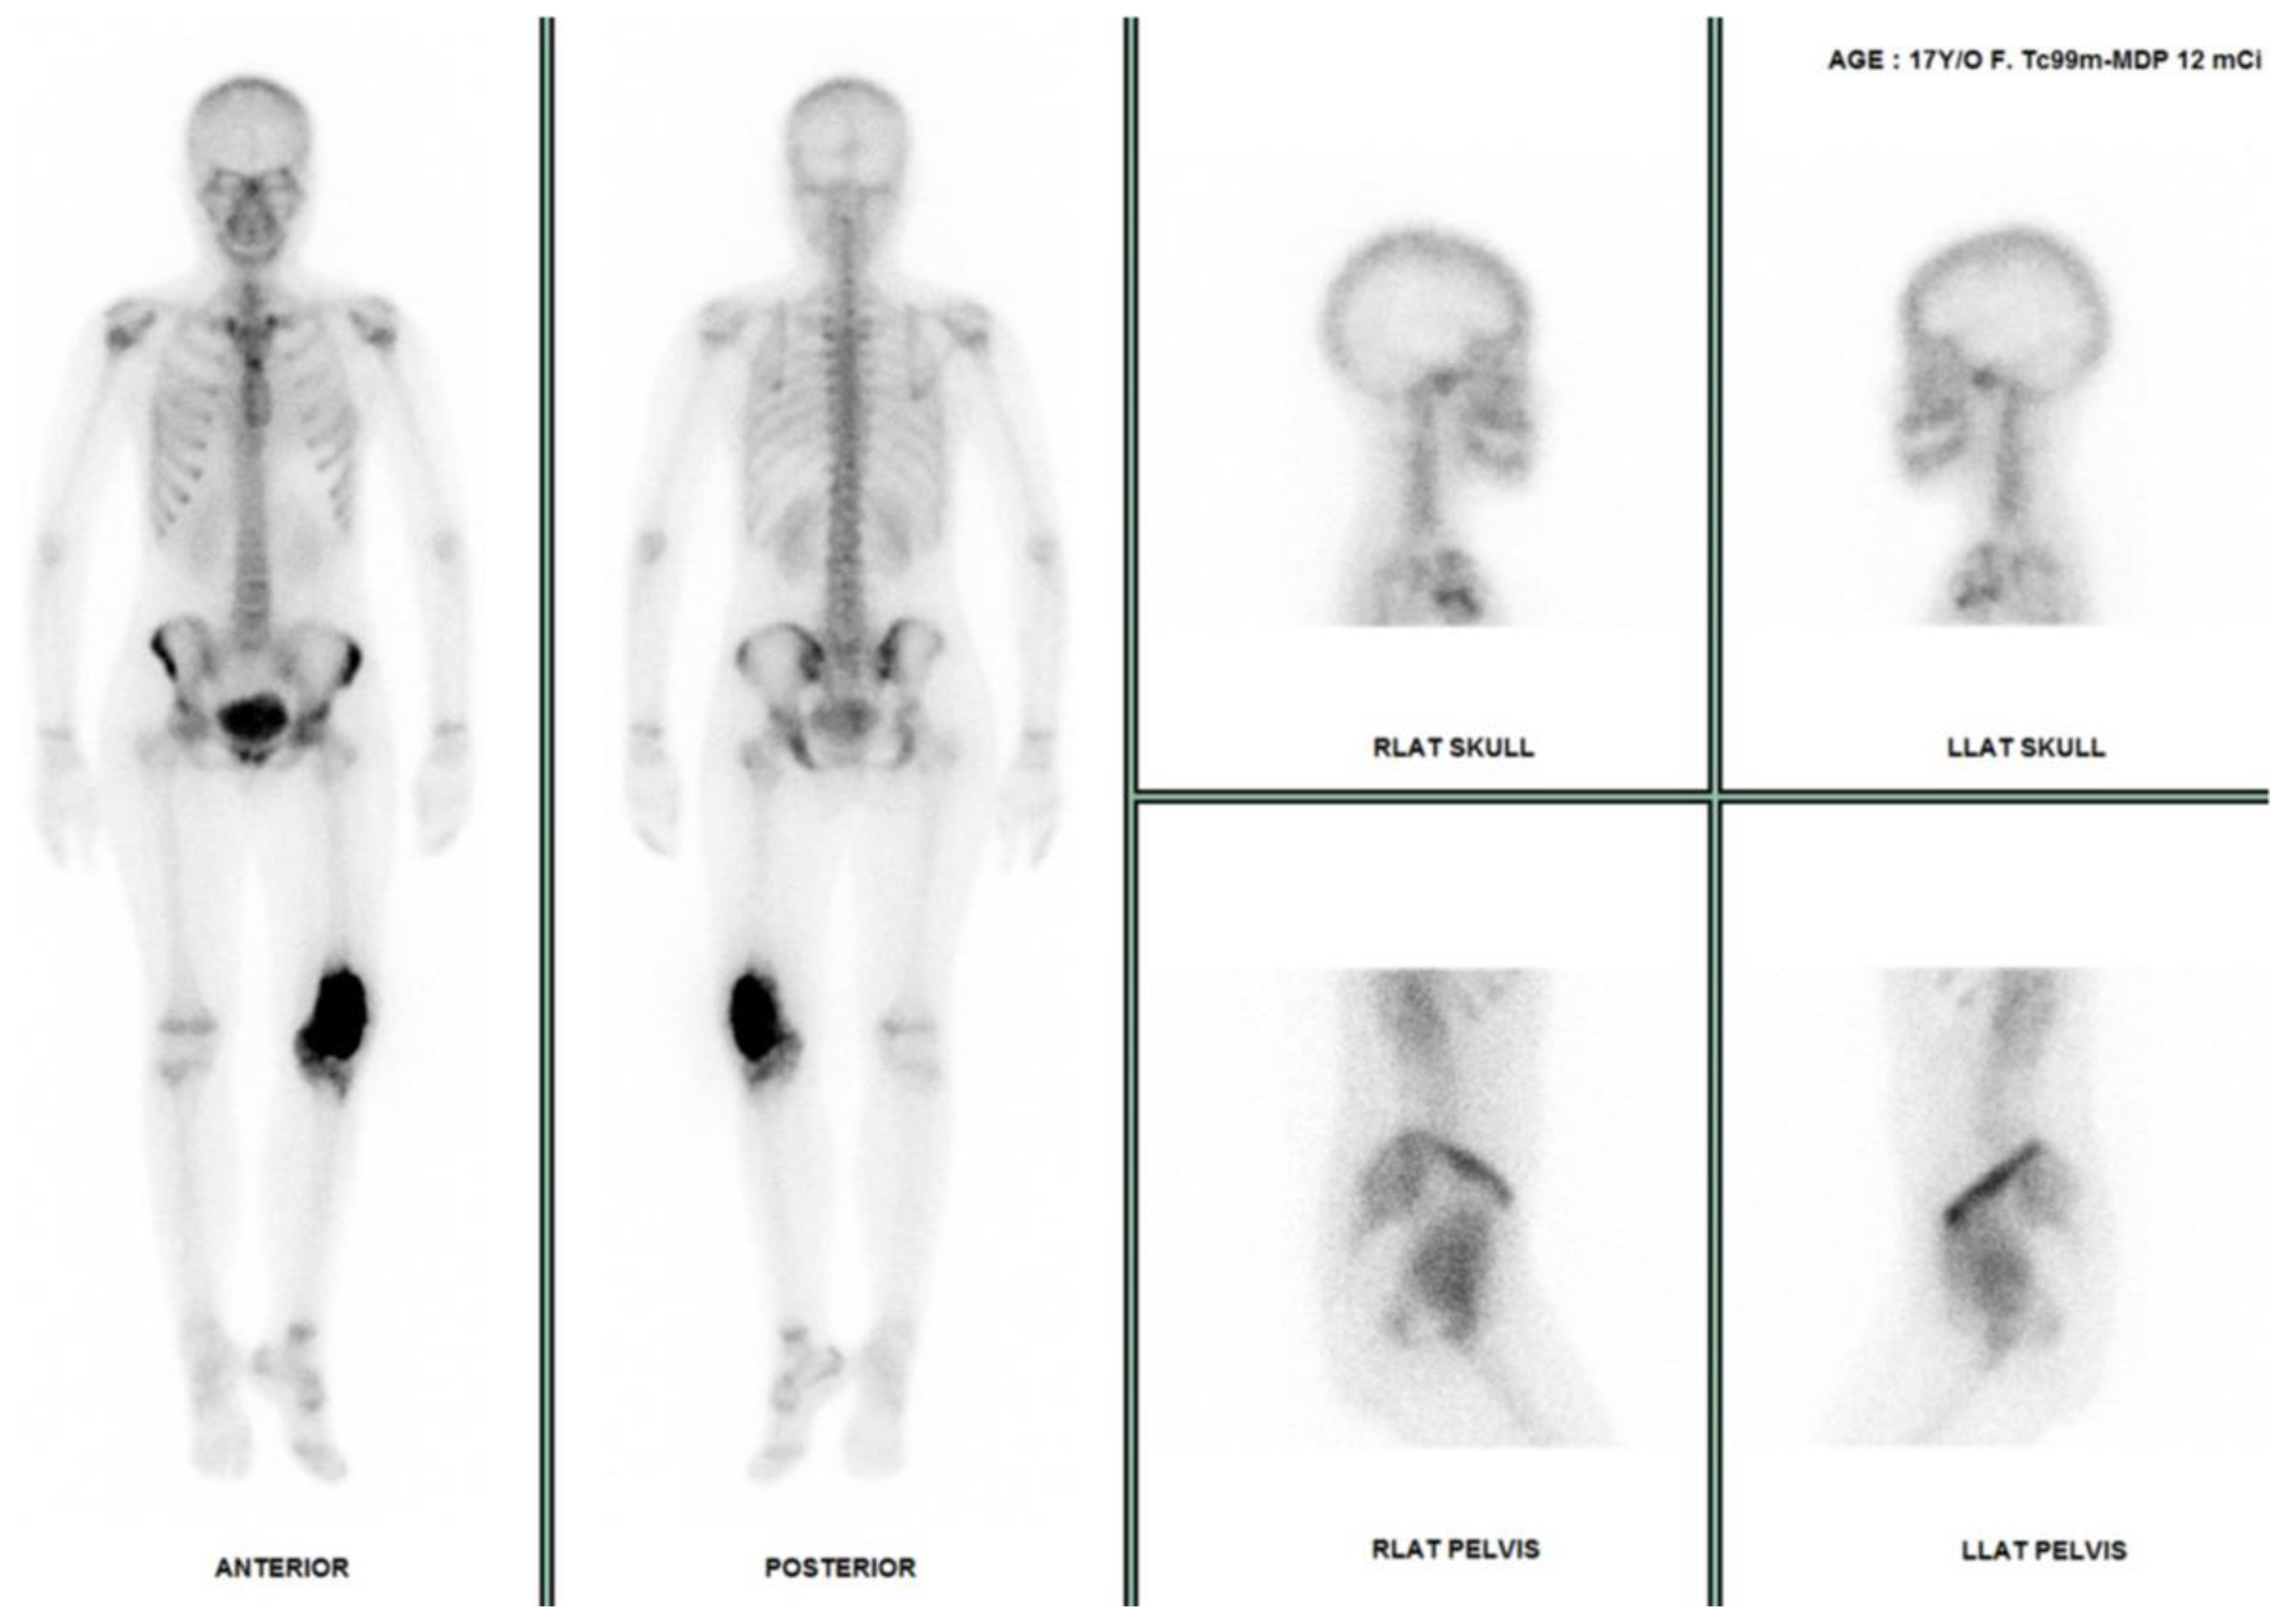

- Suthar, R.; Bharwani, N.; Pareek, P.; Salunke, A.A.; Patel, K.; Shukla, S.; Aron, J.; Kapoor, K.; Yalla, P.; Rathod, P.; et al. Role of Bone Scintigraphy (Bone Scan) in Skeletal Osteosarcoma: A Retrospective Audit and Review from Tertiary Oncology Centre. J. Orthop. 2024, 48, 20–24. [Google Scholar] [CrossRef] [PubMed]

- Hurley, C.; McCarville, M.B.; Shulkin, B.L.; Mao, S.; Wu, J.; Navid, F.; Daw, N.C.; Pappo, A.S.; Bishop, M.W. Comparison of 18 F-FDG-PET-CT and Bone Scintigraphy for Evaluation of Osseous Metastases in Newly Diagnosed and Recurrent Osteosarcoma. Pediatr. Blood Cancer 2016, 63, 1381–1386. [Google Scholar] [CrossRef]

- Oh, C.; Bishop, M.W.; Cho, S.Y.; Im, H.-J.; Shulkin, B.L. 18 F-FDG PET/CT in the Management of Osteosarcoma. J. Nucl. Med. 2023, 64, 842–851. [Google Scholar] [CrossRef] [PubMed]

- Aryal, A.; Kumar, V.S.; Shamim, S.A.; Gamanagatti, S.; Khan, S.A. What Is the Comparative Ability of 18F-FDG PET/CT, 99mTc-MDP Skeletal Scintigraphy, and Whole-Body MRI as a Staging Investigation to Detect Skeletal Metastases in Patients with Osteosarcoma and Ewing Sarcoma? Clin. Orthop. Relat. Res. 2021, 479, 1768–1779. [Google Scholar] [CrossRef] [PubMed]